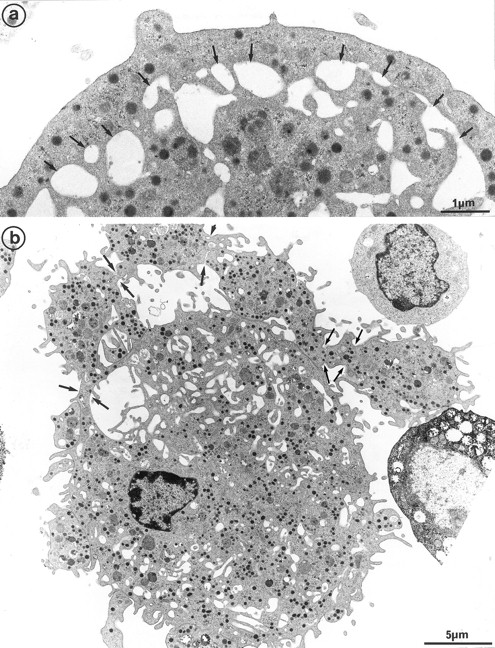

The second population had not been observed by us in any other culture conditions before the use of Mpl-l. It is noteworthy that the described morphologic changes were also present in single cell experiments, ruling out the necessity of other cytokines produced by accessory cells (not shown). A mean of 15% of the MKs had a tighter nucleus with closely apposed nuclear lobes and an indented shape, the chromatin being mostly condensed. The cell surface was uneven, often bristled with thin pseudopods. The appearance of these cells was consistent with their undergoing active platelet shedding. But because electron microscopy takes point-in-time looks at continually changing processes, dynamic relationships could only be inferred from electron microscopic data. Nevertheless, the following morphologic events were observed, leading to the eventual platelet shedding: (1) Alignment and dilatation of the peripheral demarcation membranes (Fig 3a). (2) Unfolding of cytoplasmic sheets and extension of cytoplasmic expansions still attached to the cell body, equivalent to “proplatelets” (Fig 3b). (3) These extensions could be several within a cell, and appeared to be most often still attached to the cell body. (Some large proplatelet-like territories appeared to be separated from the cell core, but this might be an artifact related to the section plan.) The cytoplasmic extensions displayed a beaded appearance, with constriction points separating discrete platelet-like territories. Along a proplatelet, future platelet delimited areas were decreasing from 10 μm to 2 μm in size, the smaller being the furthest from the cell core and the earliest to detach (Fig 4). (4) Careful observation of the constriction zones showed that MK cytoplasmic extensions elongated with the appearance of a central longitudinal bundle of microtubules (Fig 5). Immunogold labeling for tubulin was able to evidence this structure. (5) Some microtubules, transverse to the long axis of the cytoplasmic extension, appeared on both sides of the constriction zone (again confirmed by tubulin immunolabeling); and a central vacuole formed and widened in the constriction zone center, leading to the further detachment of a newly formed platelet (Fig 5). (6) Platelets of various size were found in the supernatant of the culture medium. We have studied this shed platelet population by electron microscopy and immunoelectron microscopy (Fig 6).

Cultured MK grown for 7 days from CD34+CD38+ progenitors in the presence of Mpl-l, and presenting signs of platelet formation. (a) This mature MK displays alignment and dilatation of some peripheral demarcation membranes, individualizing an outer ring of cytoplasm (arrows). (b) The peripheral sheet of cytoplasm has unfolded from the cell core. Constriction zones are regularly disposed along this cytoplasmic extension (arrows).

Sample of cultured MK grown for 7 days from CD34+CD38+ progenitors in the presence of Mpl-l, showing some evidence of platelet formation and shedding. (a) A cytoplasmic process extends straight from the cell core. Constriction zones seem to individualize already distinct platelet fields of large size, close to the MK core (arrows). (b) The appearance of this mature MK is consistent with the process of shedding platelets: The nucleus (N) displays condensed heterochromatin, and its shape is indented. Several platelet-sized cytoplasmic fragments have clearly detached from the MK (P). A large cytoplasmic fragment deprived of nuclear material and possibly corresponding to a detached proplatelet (PP) is also shown. (c) Before releasing platelets, a constriction zone (arrowheads) is formed between the mother cell and the forming platelet (P′). A few detached platelets (P) seem to have already detached, as well as numerous microparticles (arrows). (d) Considerable dilatation of the demarcation membrane system (dm) leads to the demarcation of future platelet fields (P).